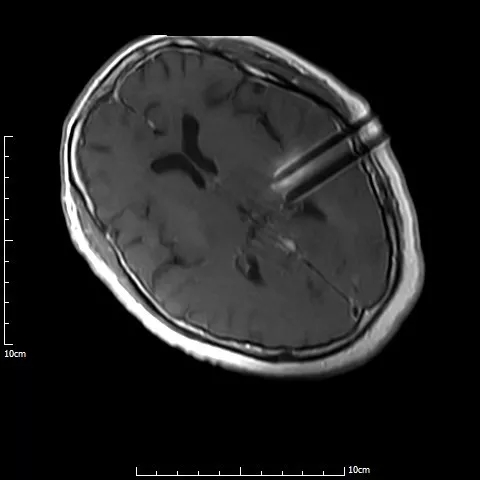

磁共振介入诊疗手术室

3D打印模板术中定位

介入手术治疗中,

磁共振实时引导技术保证介入手术过程在可视化下连续性完成

手术过程仅半小时,先对满女士进行局麻,然后在1.0T开放式介入磁共振监控及3D打印模板引导下,

李成利主任将4根磁共振兼容性穿刺针平行穿刺至肿瘤病变既定位置,根据近距离放疗计划植入I125放射性粒子,